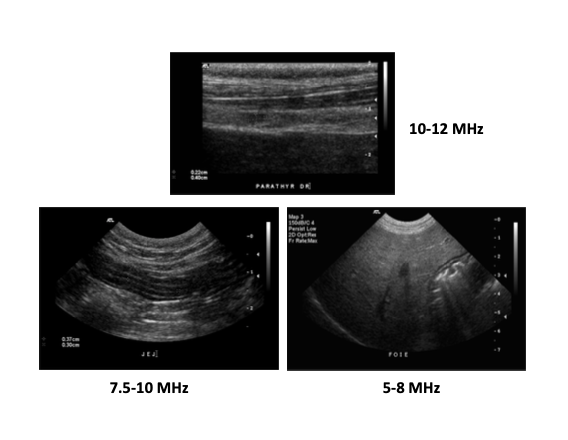

Quelle est l’importance de la résolution des sondes?

A

=> Résolution : capacité d’un système à différencier 2 structures rapprochées. Proportionnelle à $$$

=> impact important sur :

• qualité des images

• capacité à évaluer les structures

• détection et caractérisation des lésions